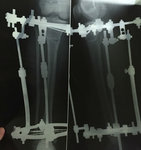

Диагноз: ахондроплазия, варусная деформация обеих голеней 155 градусов.

26 лет.

Дата операции 08.07.2015г.

Исходник.